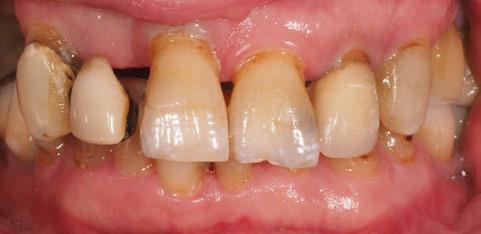

A partir del estudio radiológico y de las imágenes fotográficas podemos observar edentulismo de 17, 15, 14, 12,

Figura 1a. Foto intraoral frontal inicial.

Figura 1b. Foto intraoral lateral izquierda inicial.

Figura 1c. Foto intraoral lateral derecha inicial.

25, 26, 28, 37, 38, 47 y 48. Presentaba corona desajustada en 13 con extensión en 12, implantes en 35-36, 45-46, con coronas ferulizadas en 35-36, 45-46, y dientes anteriores superiores con enfermedad periodontal Grado IV.

2. Exploración de tejidos blandos

El paciente presentaba biotipo periodontal grueso, con márgenes asimétricos, con recesiones gingivales a nivel de 11 y 13 y pérdida de tejidos blandos interproximales.

3. Exploración de tejidos duros

En la exploración radiográfica (OPG, CBCT) observamos la existencia de pérdida ósea interproximal, lesión apical a nivel de la raíz mesial del 27 y el cordal del primer cuadrante incluido y neumatización sinusal del primer y segundo cuadrante.

En el CBCT observamos pérdida ósea posterior superior debida a la neumatización de los senos maxilares izquierdo y derecho. También podemos observar disponibilidad ósea apical suficiente en dientes antero-superiores para la realización de una Implantología inmediata y corticales vestibulares y palatinas conservadas.